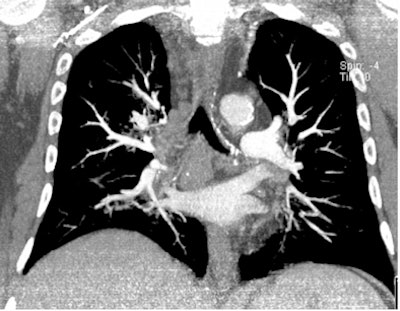

| All three CT images are from the same female patient weighing 95 kg with no pulmonary emboli. Above are two coronal maximum intensity projection (MIP) images, and below is a 1-mm thin transverse slice. At this body weight, 80-kVp CT angiography protocols provided good image quality and a high enough diagnostic confidence to exclude pulmonary embolism. All images courtesy of Dr. Zsolt Szücs-Farkas. |